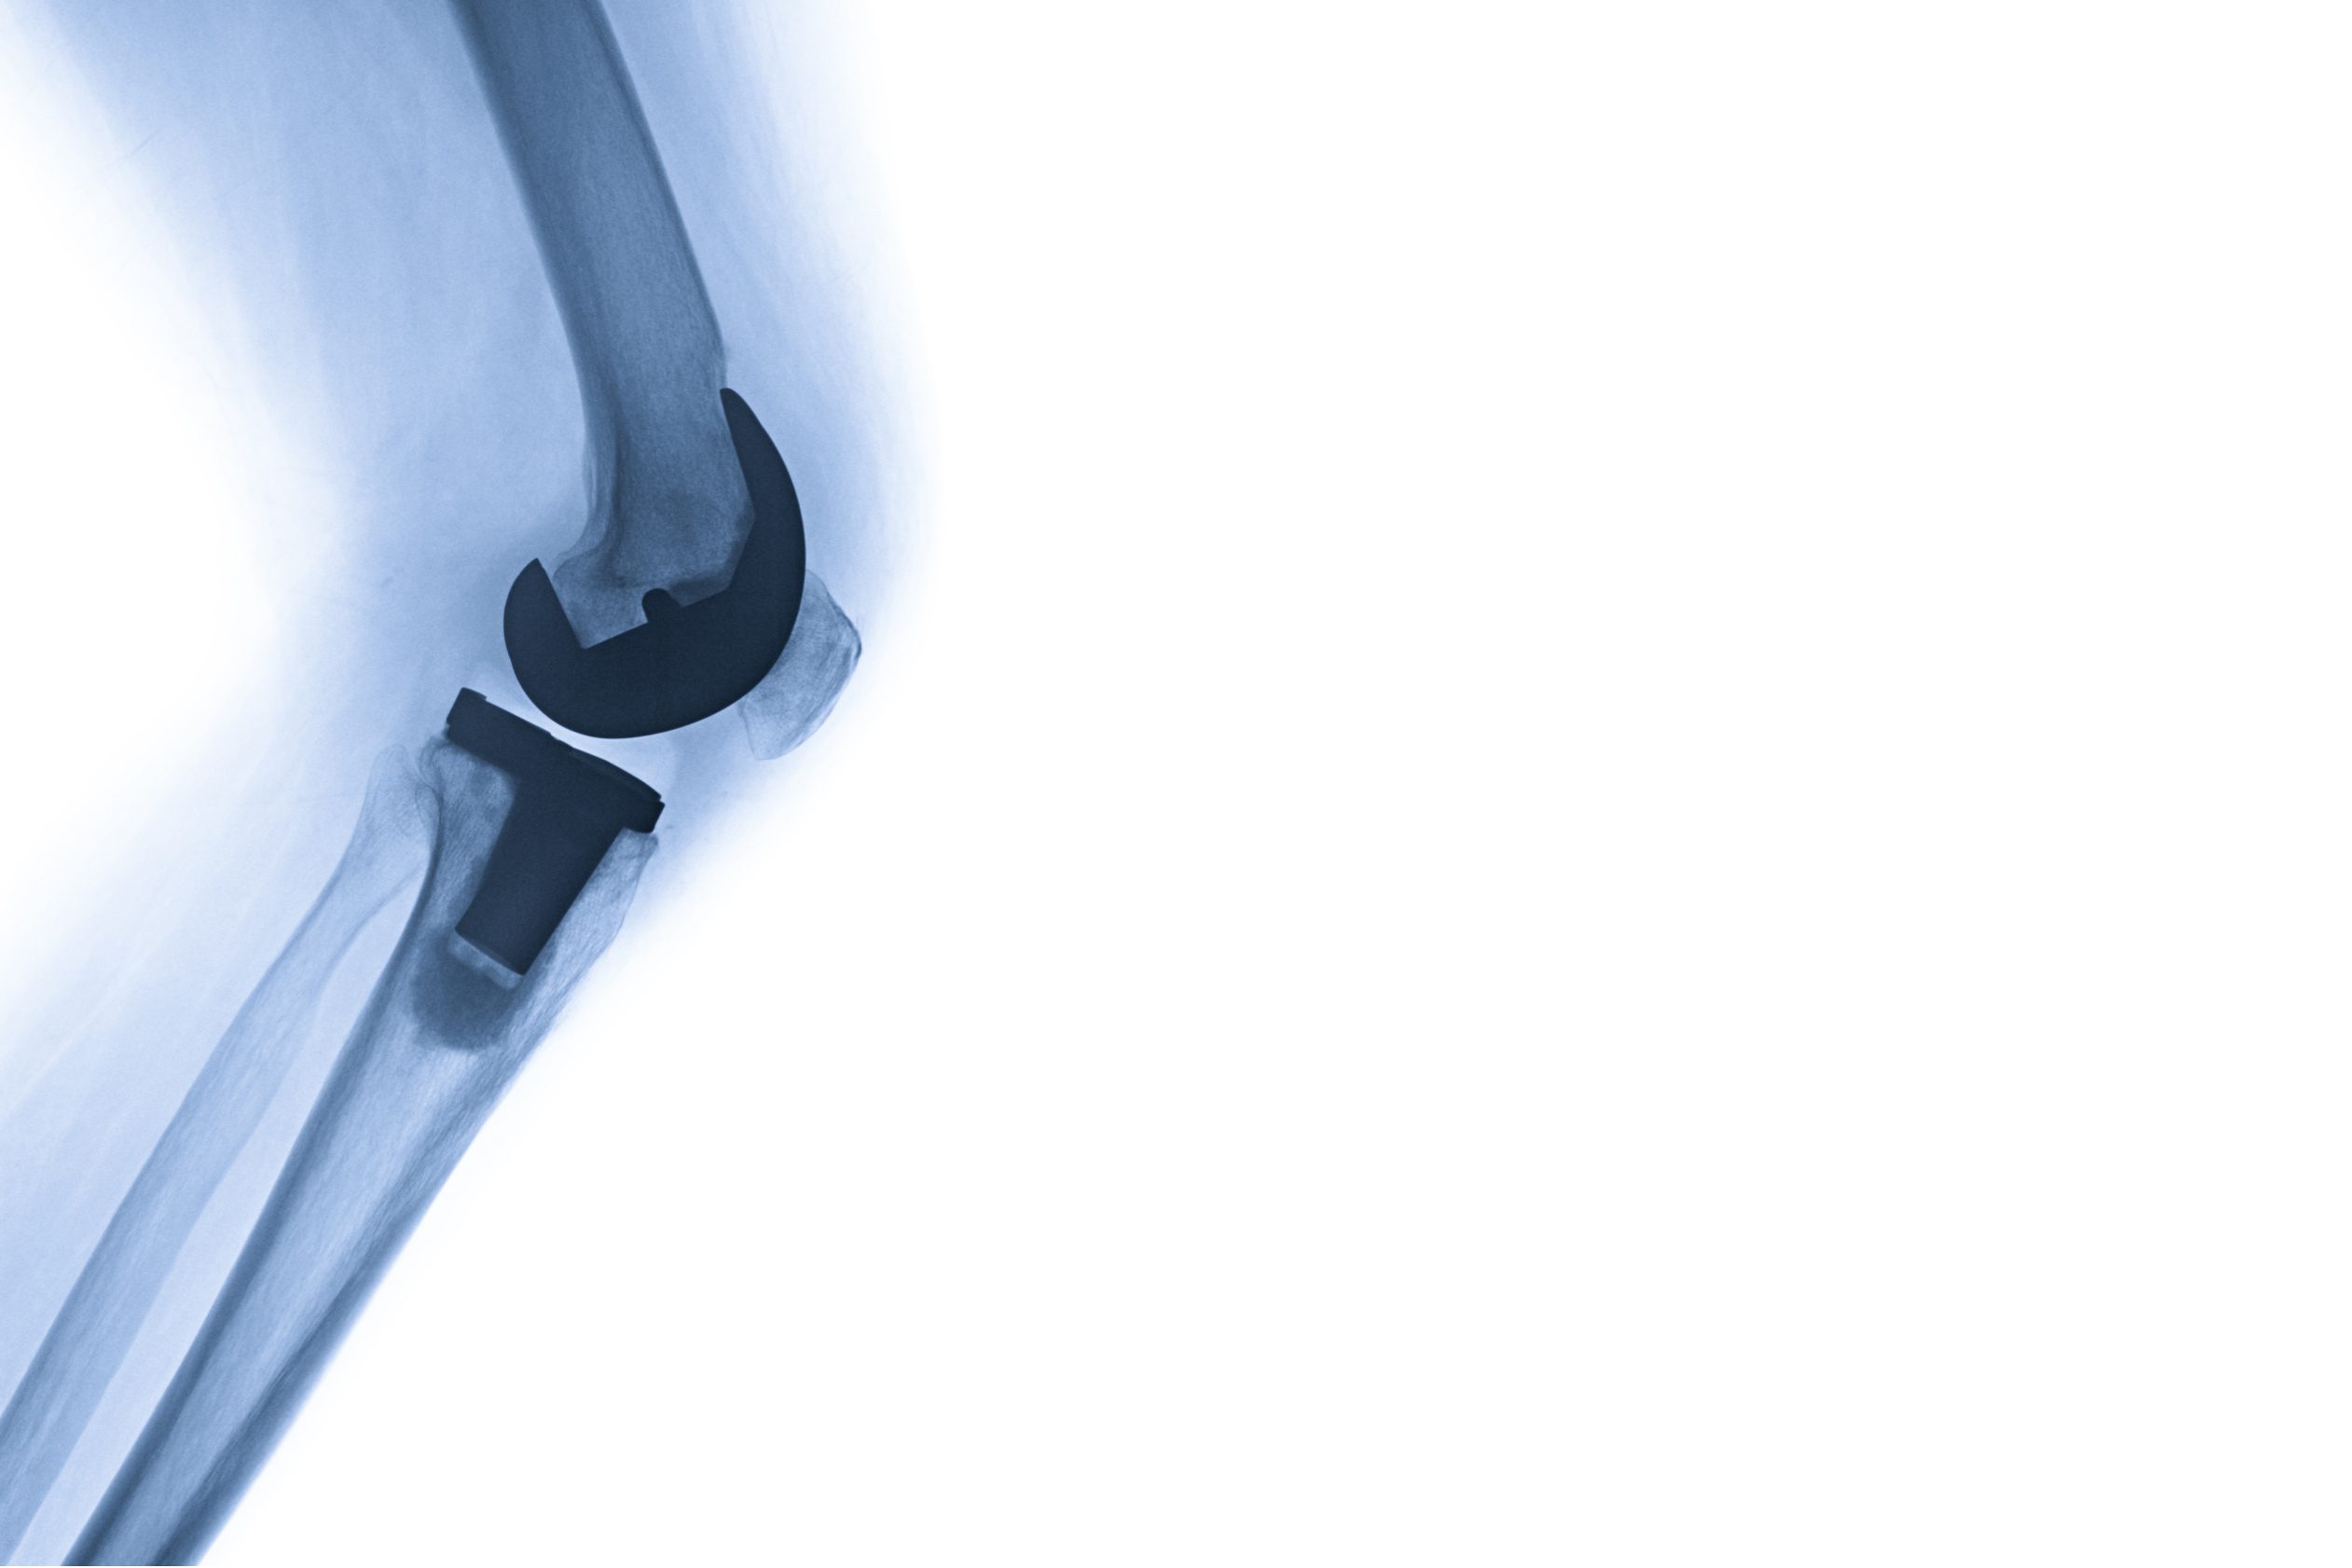

Bij de behandeling met een knieprothese kunnen enkele bijwerkingen en mogelijke complicaties optreden. Het is belangrijk dat de deelnemer en behandelend arts deze gezamenlijk bespreken. Hieronder volgen de belangrijkste bijwerkingen.

Het kan gebeuren dat de knieprothese loskomt. Mogelijke oorzaken hiervan zijn bijvoorbeeld overmatige belasting, slijtage, infectie van het gewicht, botbreuk of instabiliteit van de prothese.